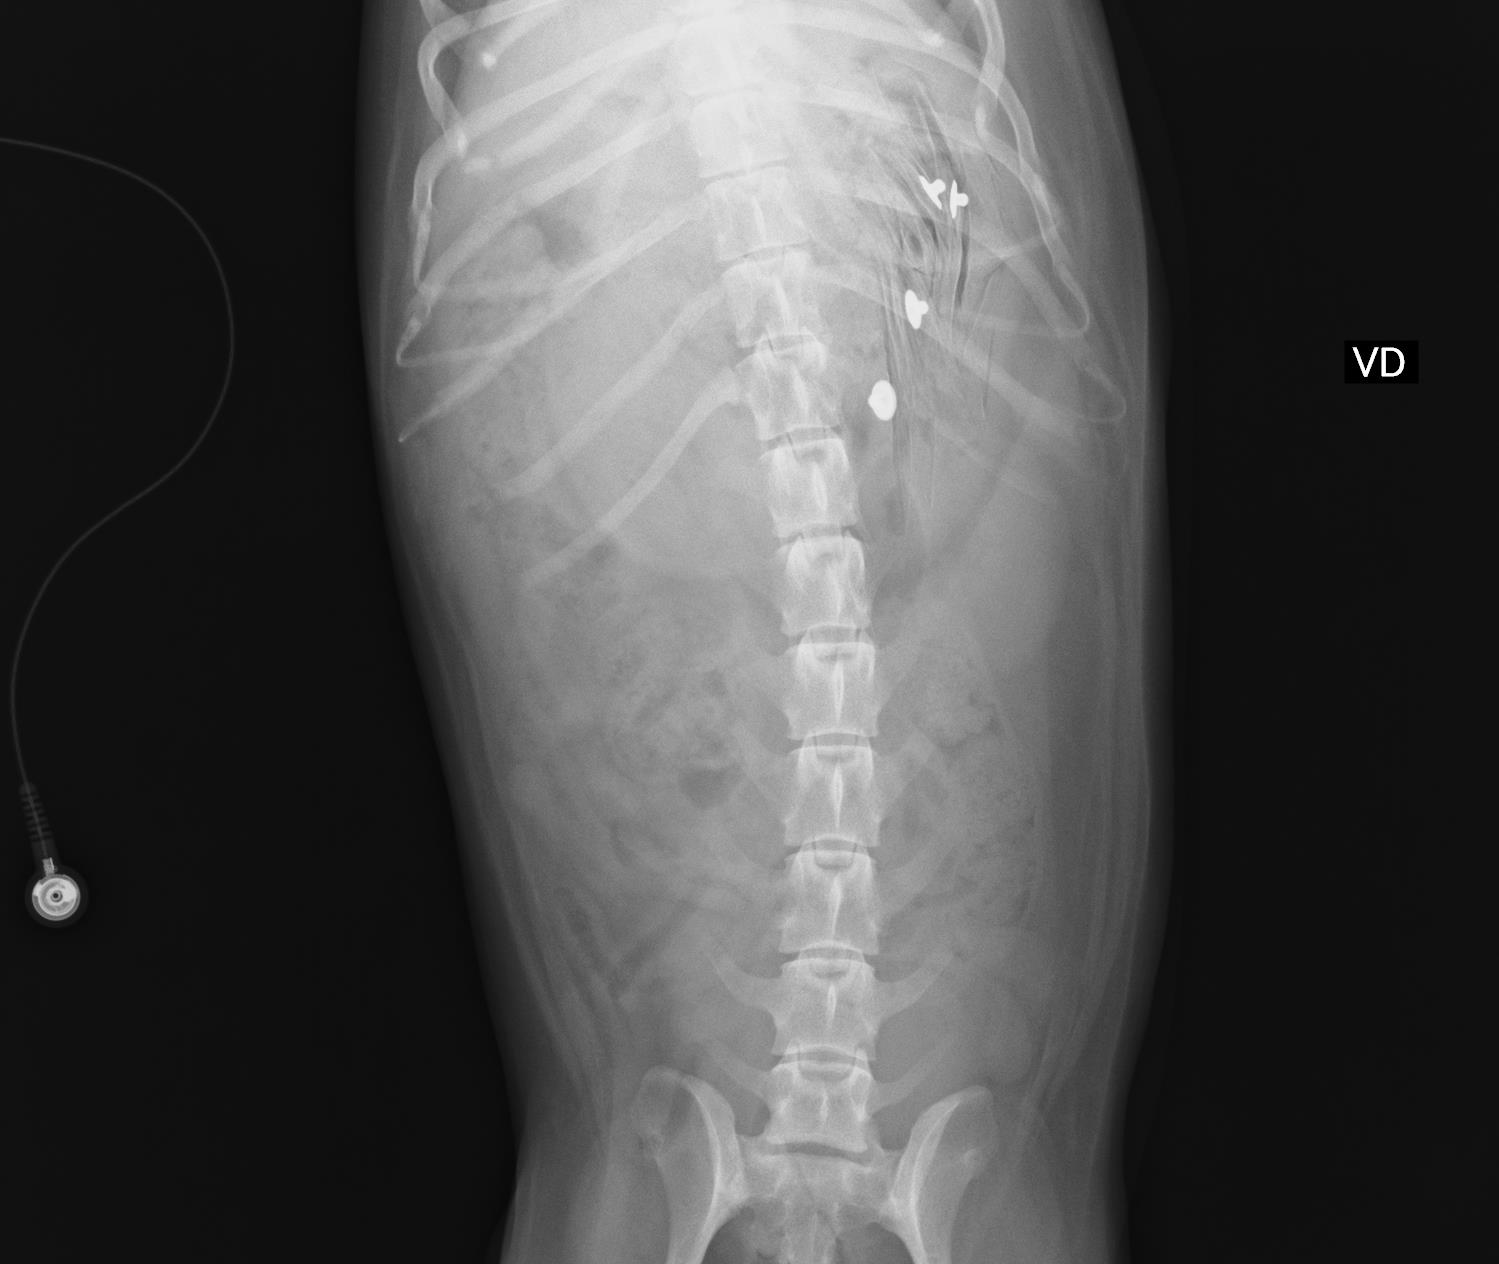

犬の異物誤飲 その4 線状異物 愛知県で犬の診療が土日祝日も可能な動物病院はもねペットクリニック